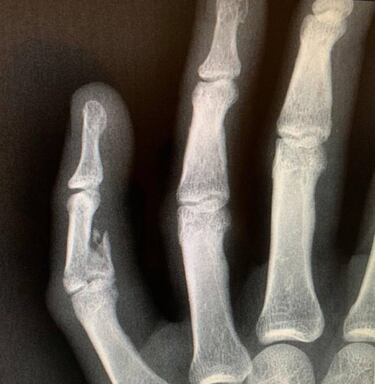

Vasco Da Gama podrá contar con Fredy Guarín para el partido de este jueves ante Goiás por la tercera ronda de la Copa de Brasil. El colombiano jugará con la mano derecha inmovilizada luego de sufrir una fractura en el dedo meñique el pasado 5 de marzo en el partido ante ABC.

La fractura de Guarín se presentó ante ABC en una jugada que lo obligó a dejar el campo al minuto 65, en el que era su segundo partido en lo que va del año con Vasco, luego de oficializar su continuidad en el equipo y adaptarse físicamente.